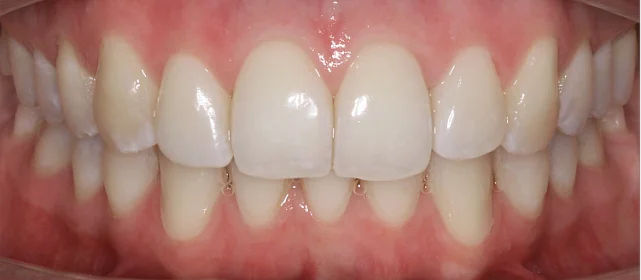

Диагностика

Верхняя челюсть выступала вперёд относительно нижней с обеих сторон (II класс по Энглю). Обе челюсти сужены, зубы стояли скученно. Нарушена кривая смыкания — жевательные зубы были на разной высоте. На двух передних зубах верхней челюсти ранее установлены металлокерамические коронки.

Результат

Зубы выровнены, скученность устранена, прикус исправлен, линия смыкания нормализована. Ретейнер установлен на нижнюю челюсть. На верхней ретейнер не ставили — на передних зубах коронки, вместо этого изготовлены ретенционные капы на обе челюсти. Пациентка направлена к ортопеду для замены коронок.

Проблема: Пациентку беспокоили неровные зубы и неправильный прикус. При осмотре нашли сразу несколько проблем: обе челюсти сужены, зубы стоят скученно, верхняя челюсть выступает вперёд (II класс по Энглю), кривая смыкания деформирована — жевательные зубы на разной высоте. На двух передних зубах верхней челюсти стояли старые металлокерамические коронки, которые нужно было учитывать при планировании.

Решение: Поставили элайнеры Click на обе челюсти. Основной набор — 31 капа, плюс два дозаказа: 26 и 7 кап, итого 64. При этом лечение уложилось в 20 месяцев — быстро для такого объёма работы. Расширили дуги, убрали скученность, исправили прикус, выровняли линию смыкания. Ретейнер поставили только на нижнюю челюсть. На верхней от ретейнера отказались сознательно — на передних зубах коронки, и проволока там не ляжет корректно. Вместо этого изготовили ретенционные капы на обе челюсти. Ортопедию — замену старых коронок — пациентка будет проходить у себя в городе.